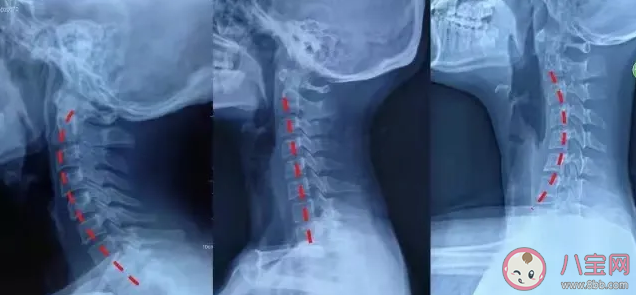

很多癥狀都可能是頸椎反弓的結果,但初期的頸椎反弓卻不一定有癥狀。" 這是因為,剛剛患上頸椎反弓時,肌肉還沒有完全疲勞僵硬,還能‘帶得動’頭部正常活動。" 可是如此說來,頸椎反弓豈不是難以早發現早預防了?想要判斷自己是否發生了頸椎反弓,盡管在醫院拍片是最清晰的方式,但是在家也可以通過簡單的測試對自己的頸椎情況了解一二。

" 醫生判斷是否發生頸椎反弓時,可以在人的耳朵前側掛一條鉛垂線,自然站立位下,如果鉛垂線超過了胸骨頂端,可能就是頸椎過度前傾反弓了。" 而在家中,即使沒有鉛垂線,也能做一個大體的判斷:" 可以自然靠墻站立,不要仰頭,也不要低頭,雙眼平視前方。讓另一個人從側面觀察你頭和墻之間的距離,如果頭部離墻越遠,頸椎反弓的可能性就越大。"